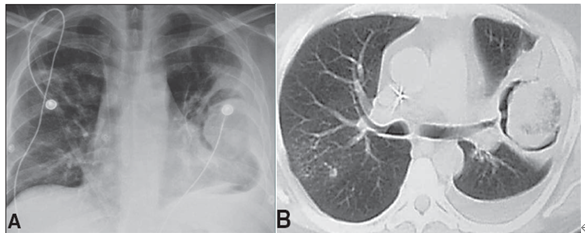

诊断、治疗、预后

诊断

在影像学方面,虽难以与侵袭性肺曲霉相鉴别,但多具有以下特征性表现:10个或更多部位的多发结节;胸腔积液;反晕征;与肺梗死毗邻的蜂窝组织炎。使用荧光增白剂的直接镜检临床样本可快速诊断,镜下可见菌丝粗细不均(6~25 μm),无分隔或很少分隔,不规则的带状外观[6]。样本的培养视为基本的检测方法,虽然敏感性不是最佳,但可用于鉴别诊断和药敏试验。强烈推荐组织样本的病理学检测用于区别曲霉菌、形态类似真菌及不同毛霉菌,从而指导临床治疗[6]。其他包括DNA测序和PCR等分子技术在诊断方面尚未标准化,也未获得专家认可[7]

毛霉菌病的确诊主要通过真菌病原学和组织病理学,最终诊断依赖于病理发现并经培养证实,但培养的假阴性多。组织病理学或涂片常成为诊断的唯一证据。G试验、GM试验等在毛霉菌感染时均为阴性。